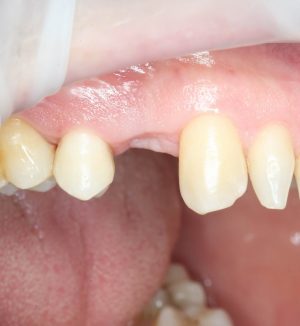

Для окончательного формирования десневого контура, осталось только наложить швы.

Наложение швов.

Помните, в самом начале операции мы планировали наложение швов с учётом будущего вестибулярного смещения лоскута? Так вот, теперь у нас есть возможность не просто сместить, но и зафиксировать вестибулярный лоскут. Делается это, так сказать, с подворотом края снаружи:

Обратите снимание, что альвеолярный отросток в этой области стал более объемным. Этого удалось добиться без всяких остеопластических операций или гингивопластики, путём простого перемещения тканей.